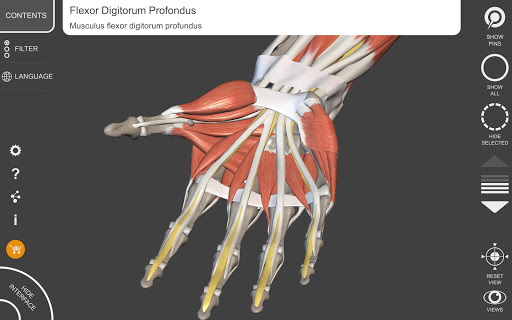

"Anatomy 3D Atlas" vous permet d'étudier l'anatomie humaine de manière simple et interactive.

Grâce à une interface simple et intuitive, il est possible d'observer chaque structure anatomique sous n'importe quel angle.

Les modèles anatomiques 3D sont particulièrement détaillés et avec des textures jusqu'à une résolution de 4k.

• Système musculo-squelettique

• Faites pivoter et zoomez chaque modèle dans l'espace 3D

• En sélectionnant un modèle ou une épingle, le terme anatomique associé apparaît

• Description des muscles : origine, insertion, innervation et action

• Les termes anatomiques et l'interface utilisateur sont disponibles en 11 langues : latin, anglais, français, allemand, italien, portugais, turc, russe, espagnol, chinois, japonais et coréen

• Les termes anatomiques peuvent être affichés en deux langues simultanément